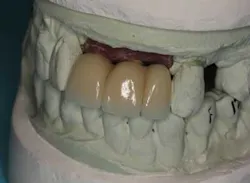

Fig. 11

From a restorative perspective, now that the implants were placed in a restoratively driven manner, the main considerations were to address the patient’s malocclusion and correct her edge-to-edge bite while delivering optimal esthetics. In order to accomplish this goal, a framework was fabricated with a wax-up on the casts. (Fig. 14) By utilizing this method at the framework try-in visit, we were able to give the patient an extremely accurate preview of what her final prosthetic would look like.